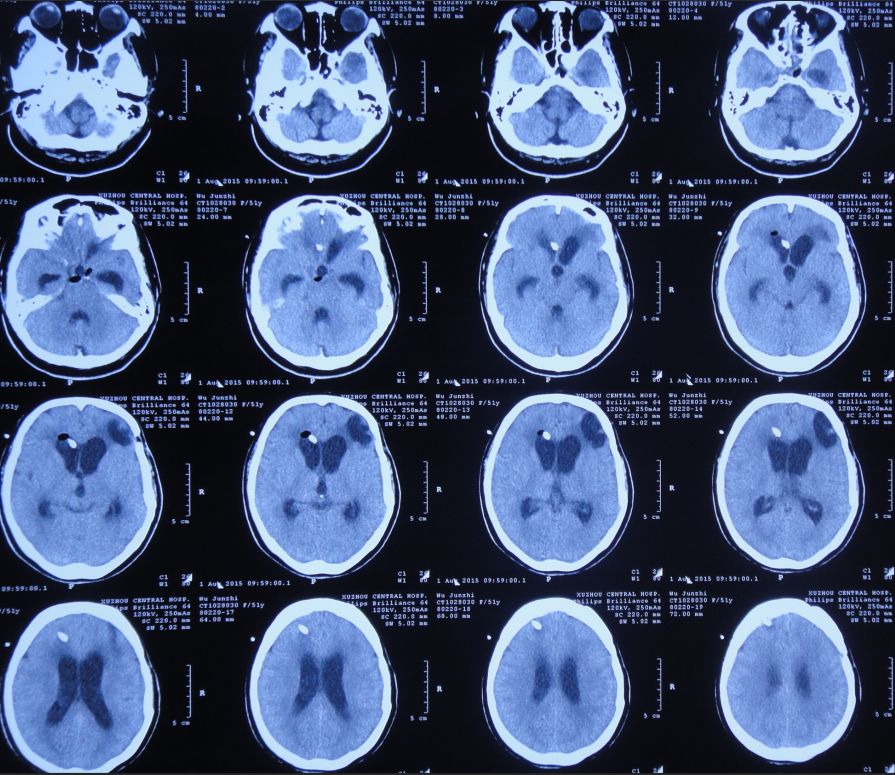

胆囊造瘘术后第56天即2015年12月25日,复查头CT:颅内无异常(图44)。查腹部CT:胆囊造瘘术后,改变(图45)。

图44:2015年12月25日头CT:颅内无异常

胆囊切除术后第33日即2016年1月30日,患者一般情况可,复查头CT:颅内无明显积气(图52)。

图52:2016年1月30日头CT:颅内无明显积气

分流术后第60天即2016年5月4日,患者神清,精神可,生活自理;复查头CT显示脑室恢复正常,颅内无积气(图56),办理出院。

图56:2016年5月4日头CT:脑室恢复正常,颅内无积气

出院后6个月即2016年10月24日来院复查,患者神清,精神好,思维及肢体活动完全恢复正常(图57)。复查头CT:脑室正常,颅内无积气(图58)。

图58:2016年10月24日头CT:脑室恢复正常,颅内无积气